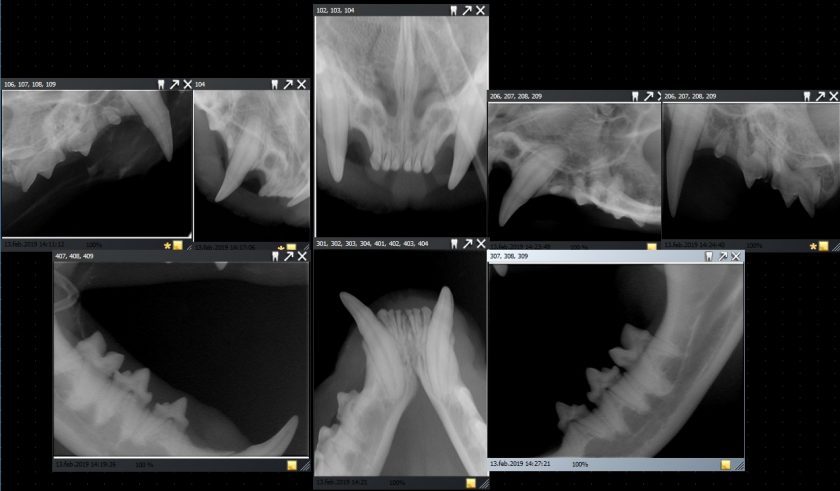

KASPER PÅ TANNSJEKK

Kasper er bare 2,5 år, men allerede var det behov for tannsjekk. Den vanligste tannsykdommen hos katt er FORL, eller TR (Tooth Resorption) som den også heter. Enkelt potert er det rett og slett kroppens celler som spiser opp tennene, og er akkurat like smertefullt som det høres ut som. Det er en gammel tannsykdom som har plaget katter i flere hundre år, og finnes både hos tamme og villkatter, rasekatter og huskatter. Visste du at: Omtrent hver 3. voksne k

HJEMME ETTER TANNLEGETUR

Alle katter som har vært i narkose, trenger litt ekstra stell og tilsyn i etterkant. Man passe på at de ikke blir kald, får tatt seg en dotur og ikke spiser så mye at de blir kvalm. At de får hvilt og slappet av så de kommer i fin form etter behandlingen hos dyrlegen. Derfor fikk ikke Kasper lov å gå ut, selv om han påsto selv at han var i strålende fin form ved hjemkomsten. Men ved ankomst hjemkomst trippet han fornøyd fra bi